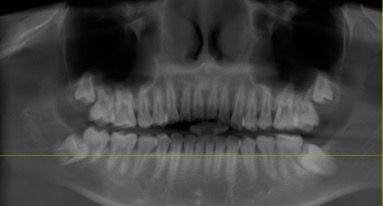

엑스레이 사진 오른쪽 아래어금니가 앞에 이를 누르고 위로 안나오는 상태인데 누운 어금니를 올리는 치료 할수 있을까요? 발치말구요..2010년생이에요

사진으로 봤을 경우에는 이미 깊게 들어가 있는 것으로 보입니다. 또한 앞의 치아에 걸려 있기 때문에 상부로 올리는 것은 힘들 것으로 생각됩니다.

사진에 보이는 치아는 수술적으로 치아에 버튼을 달아서 교정적으로 정출을 하는 치료를 하셔야될것같습니다.

치아가 그냥 누워있을 뿐만 아니라 옆 어금니 뿌리도 녹이고 있어서 상황이 좋지 않습니다 저 치아만 단독으로 세우는 건 큰 의미가 없고 왼쪽 아래 전반적으로 치료계획을 세워보면 좋을 것 같습니다